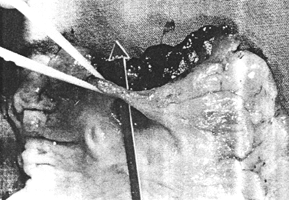

At operation considerable fibrotic reaction was encountered and the duodenum had to be dissected from the pancreas. A truncal vagotomy, antrectomy and Billroth I anastomosis was performed. The resection specimen showed a second aperture between the stomach and duodenum next to the normal pylorus, with a bridge of mucosal tissue between the 2 apertures (Fig. 31.1B) confirming the diagnosis of pyloroduodenal fistula or so-called double pylorus. Case 31.2. J.N., 55 year old male, complained of burning epigastric pain of 4 months' duration. It commenced an hour after meals and was relieved by food and antacids. There was intermittent nausea with some loss of appetite and weight. Previously he had been treated for ischaemic heart disease, gout, ethanol and aspirin abuse.

| Fig. 31.1 A,B. Case S.K. A Narrow, irregular channel between pyloric sphincteric cylinder and duodenal bulb, diagnosed as carcinoma. Normal pyloric aperture not filled with barium. Cylinder partially contracted. B Resection specimen. Arrow through pyloroduodenal fistula. Pyloric aperture visible behind arrow | |